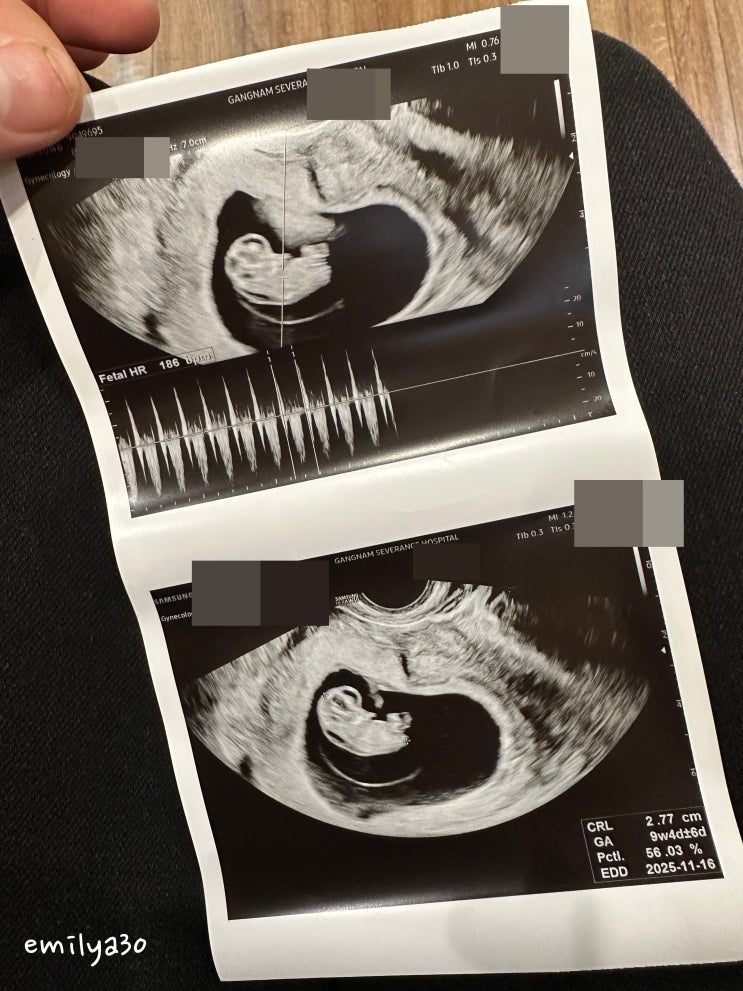

봄이 임신 9주차, 대학병원 전원 초진 !

봄이 임신 9주차, 대학병원 전원 초진 ! 임신 6주차쯤, 봄이를 만나게 해주셨던 담당 원장님은 내 기저질환...